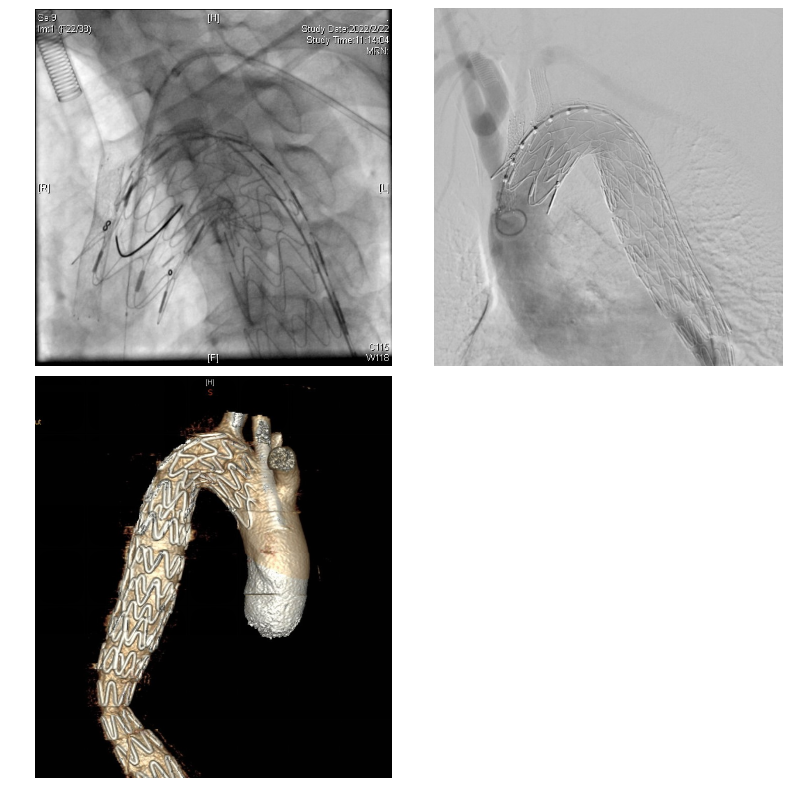

2)首先在全麻下行胸主动脉覆膜支架腔内隔绝术,锁骨下动脉支架置入术,烟囱技术左侧颈总动脉重建术。(如图4-A,B,C)

3)2周后,患者体力恢复良好,随即在全麻低温体外循环下行主动脉瓣机械瓣置换术。术中可见升主动脉及主动脉窦部正常,主动脉瓣左冠瓣及无冠瓣均有穿孔。同时,无冠瓣可见赘生物形成。(如图5-A,B)